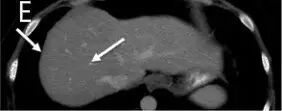

治疗1个月奇迹出现了,CT显示M女士纵隔淋巴结肿大缩小,没有新的肝或纵隔病变(图1A和B和2A和B与图1C和2C),并且在3个月时的影像学检查显示出纵隔淋巴结肿大和肝脏局部病变进一步缓解(图1D和2D)。8个月的影像显示纵隔淋巴结持续缩小,肝脏病变完全消退(图1E和2E)。患者目前仍继续进行治疗。

图1:ABCDE